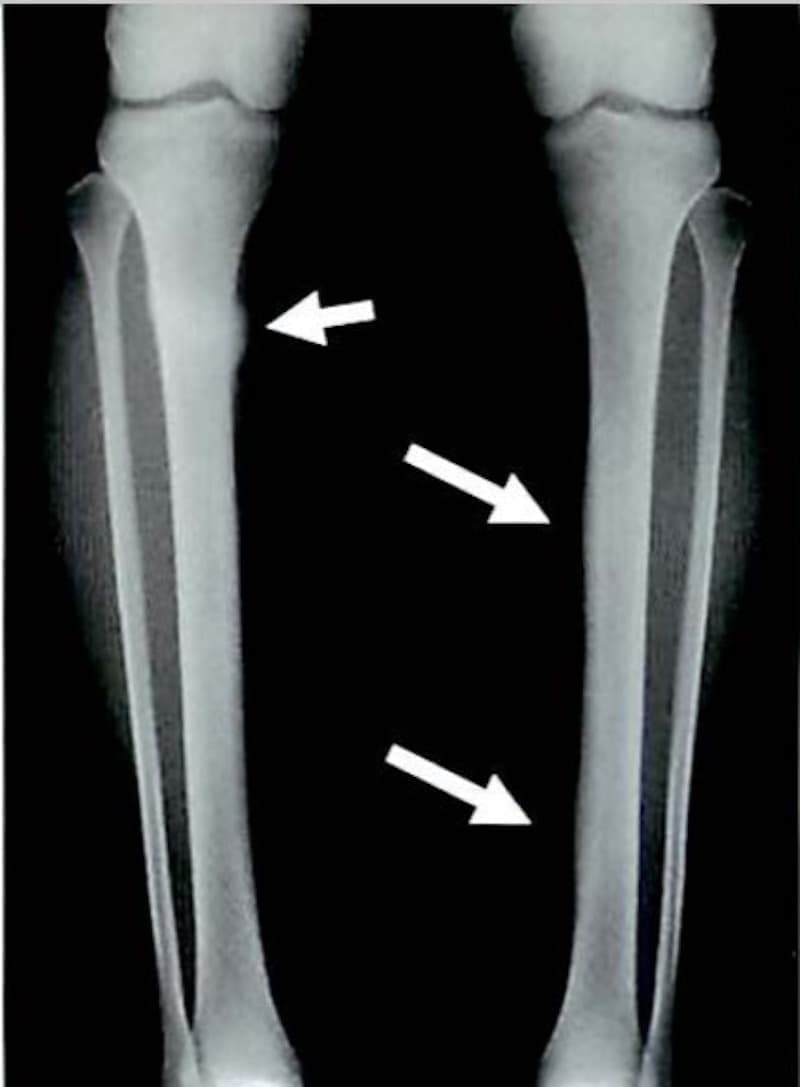

シンスプリント

別名「過労性脛骨骨膜炎」とも呼ばれます。

下腿(膝より下の足)の下部1/3の部分に起こる痛みで

ランニングを過度に繰り返すことで出現する骨膜の炎症といわれています。

痛みは脛骨に沿っての運動時の全体的な鈍痛で始まり

悪化すると通常歩行時にも痛みが出現します。

ハードなトレーニングを集中的におこなったり、硬い地面の上でランニングを繰り返す、

過剰な筋トレ、過度の足趾背屈などが原因となることが多いです。

下腿(膝より下の足)の下部1/3の部分に

起こる痛みでランニングを過度に繰り返すことで

出現する骨膜の炎症といわれています。

痛みは脛骨に沿っての運動時の全体的な

鈍痛で始まり悪化すると通常歩行時にも

痛みが出現します。

ハードなトレーニングを集中的におこなったり

硬い地面の上でランニングを繰り返す、

過剰な筋トレ、過度の足趾背屈などが

原因となることが多いです。